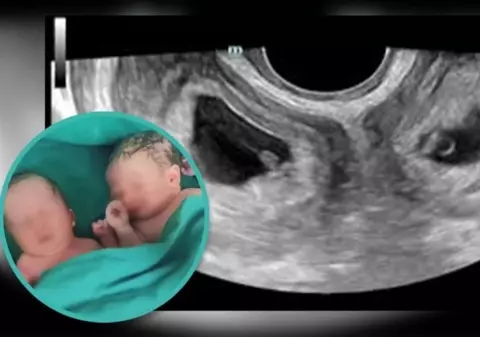

O femeie cu două utere a născut gemeni. „Un caz la un milion”, a anunțat spitalul din China